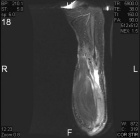

B.S. - 47 year old female with one year history of right knee pain, pain is posterior and is worse with activity, some relief with NSAID's